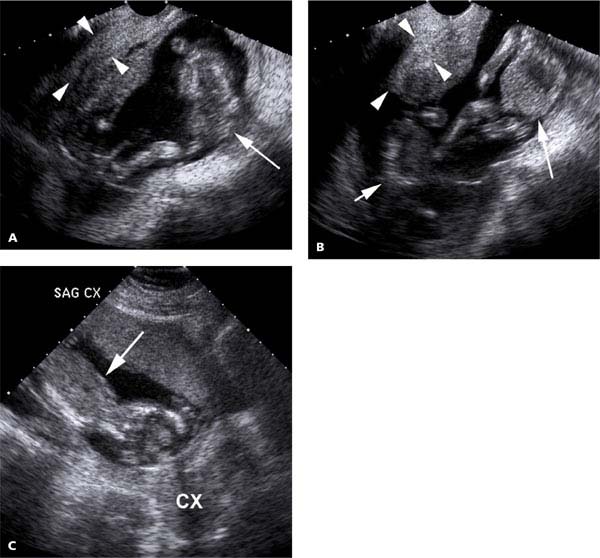

From radiologykey.com